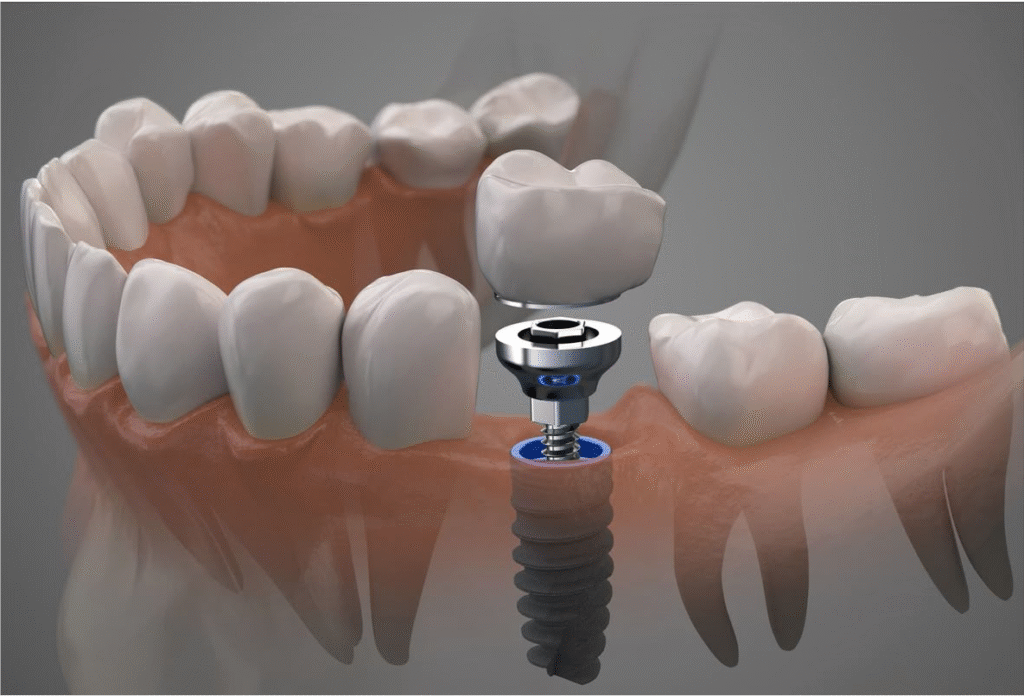

Implantología

Trabajamos con sistemas implantológicos de referencia y planificamos cada caso mediante estudios radiográficos 3D (CBCT) y, cuando procede, modelos digitales para una colocación guiada.

- Evaluación completa: análisis de hueso, salud periodontal y factores sistémicos.

- Plan digital: planificación virtual para posición y angulación óptimas.

- Cargas inmediatas o diferidas: según indicación clínica.

- Protocolo de mantenimiento: revisiones periódicas y cuidados para longevidad del implante.